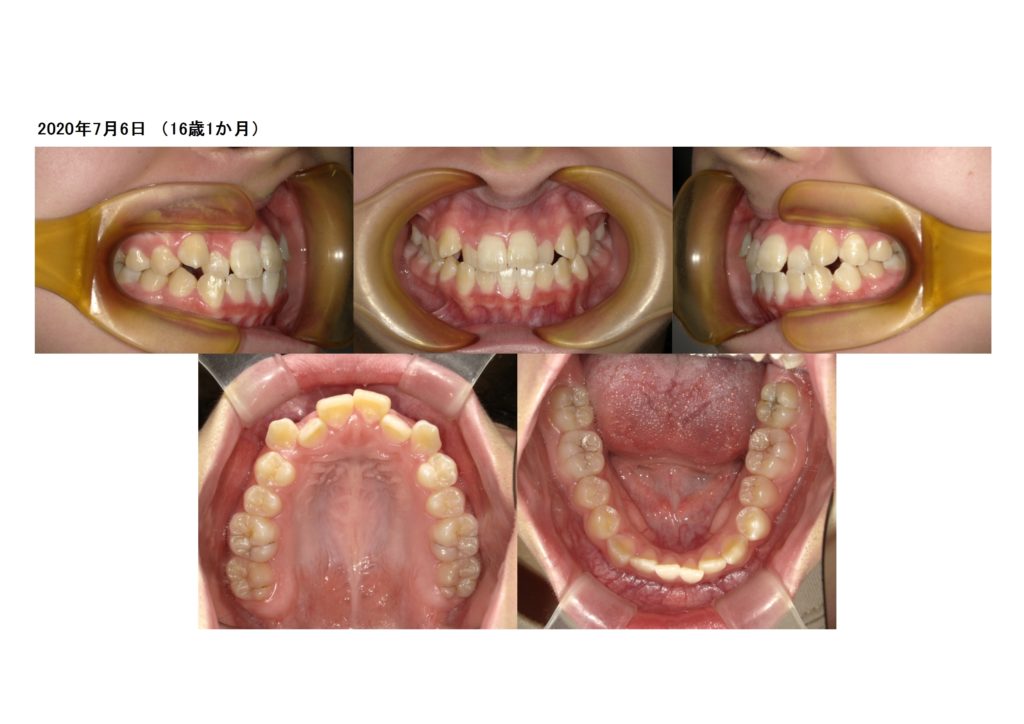

「受け口」「開咬」の噛み合わせの方は舌の癖がある可能性がとっても高いです。

矯正治療をして歯並び、噛み合わせを治すことが出来ますが、一緒に舌の癖を治していかないと、治療が進みませんし、終えることが出来ません。

このように、受け口や開咬の方は一度舌の癖を確認してみてください☆